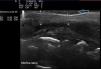

Se planteó a la familia realizarle una biopsia para la filiación de su cuadro, pero dado su compromiso estético se optó por contrastar el diagnóstico de sospecha clínica mediante ecografía cutánea. Para ello se utilizó un ecógrafo Mylab™25 (Esaote) con una sonda lineal compacta de 18Mhz, con el fin de apoyar el diagnóstico clínico y especialmente asegurar una correcta monitorización de la enfermedad. Para estudiar de forma correcta el grosor dérmico y epidérmico se aplicó una importante capa de gel, obteniendo una imagen de calidad sin necesidad de realizar presión sobre la piel, ya que esto podría falsear la imagen. En ella se visualizó una disminución de la banda epidérmica y del espacio dermosubdérmico, con incremento de la ecogenicidad de la dermis en comparación con la piel adyacente (fig. 2). No había aumento de vascularización mediante el uso del modo doppler en el área lesional. La exploración neurológica fue rigurosamente normal, y no se solicitaron pruebas complementarias analíticas. Ante el aspecto clínico y la imagen ecográfica compatible, concluimos el diagnóstico de morfea lineal inactiva y decidimos adoptar actitud expectante.

La diferencia de espesor entre la piel afectada y la piel normal no se correlaciona con la actividad de la enfermedad. De entre las diferentes características a considerar, la ecogenicidad total de la lesión, la hipoecogenicidad de la hipodermis y el aumento de vascularización de la dermis profunda parecerían correlacionarse con aumento en la actividad clínica8. Estos parámetros fueron evaluados en el presente paciente para decidir nuestra actitud terapéutica expectante. Cuando la morfea se ha estabilizado clínicamente, en la ecografía cutánea se observa una mínima diferencia de ecogenicidad global entre la piel afecta y la piel normal, como sucede en nuestro caso9,10.